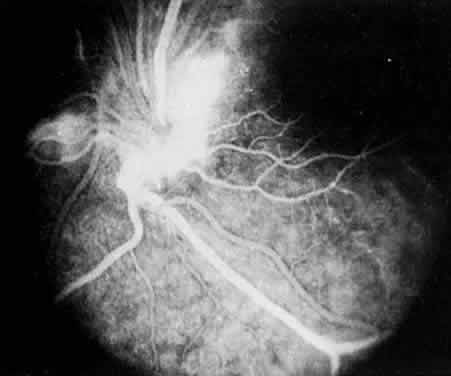

Retinal detachment, vitreous hemorrhage, optic disc swelling, and dragging of the optic disc vessels caused by contraction and neovascularization of cyclitic membranes occur in less than 10% of cases.13,52,53 Periphlebitis has been reported in about 21% of cases.52 Neovascularization of the optic disc53–55 and peripheral retina56 can also occur (Fig. 7). Coat's-like response has been reported in pars plantitis.57 Band keratopathy, glaucoma, and retinoschisis may develop as late sequelae in pars planitis.13

Fig. 7. Pars planitis. Fluorescein angiogram of neovascularization of the optic disc.